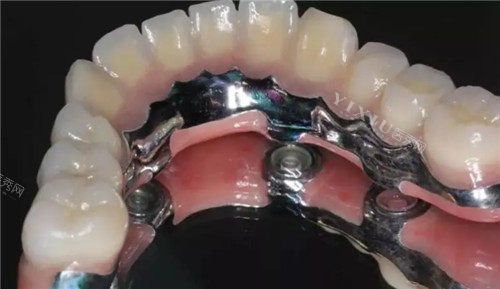

半固定种植牙通过球帽或杆卡方式进行固定,这种设计允许患者自行摘戴。可摘戴的特性使得日常清洁更为方便,患者可以取下修复体进行清洁。然而,这种结构也可能导致食物残渣更容易在连接部位积累,需要特别注意清洁。

全固定种植牙则通过粘接或螺丝固定,修复体不可摘戴。这种固定方式减少了食物残渣积累的风险,但由于不能取下,日常清洁相对困难,需要使用特殊的清洁工具和方法来维护口腔卫生。